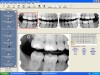

Infection Control—Typically, the receptor instruments can tolerate sterilization methods such as steam autoclaving before reuse. Digital receptors cannot be sterilized so the clinician must adhere to careful disinfection and barrier coverage techniques to avoid direct and cross-contamination of the receptor. The standard spray-wipe-spray or immersion disinfection technique is not appropriate for sensor preparation. Wiping rigid digital sensors with a mild disinfectant agent before barrier placement is thought to be an acceptable disinfection practice.25 When in doubt, refer to the manufacturer’s instructions regarding recommendations for sensor preparation and protection prior to use. PSP plates should be inserted into a barrier envelope and sealed before placement in the mouth. After removal, the barrier should be cleaned with disinfectant hand soap and water and then dried.26 Following glove removal and hand washing, the barrier should be opened carefully and the plate dropped out with the sensitive side down into transfer carrier.26 The clinician should be observant during the radiographic procedures to ensure that the barrier does not become torn during instrumentation. Table 1 presents the basic steps involved in intraoral digital imaging. An example of a patient file is depicted in Figure 3. The act of saving the image is similar to saving any file on a computer system.

Figure 3. One of the steps in digital imaging is to create a patient file in the computer software to acquire and archive radiographic images. In this example, a bitewing template was selected, and then the images were captured and displayed on the monitor. (Patterson Dental Supply, Inc)

Figure 3